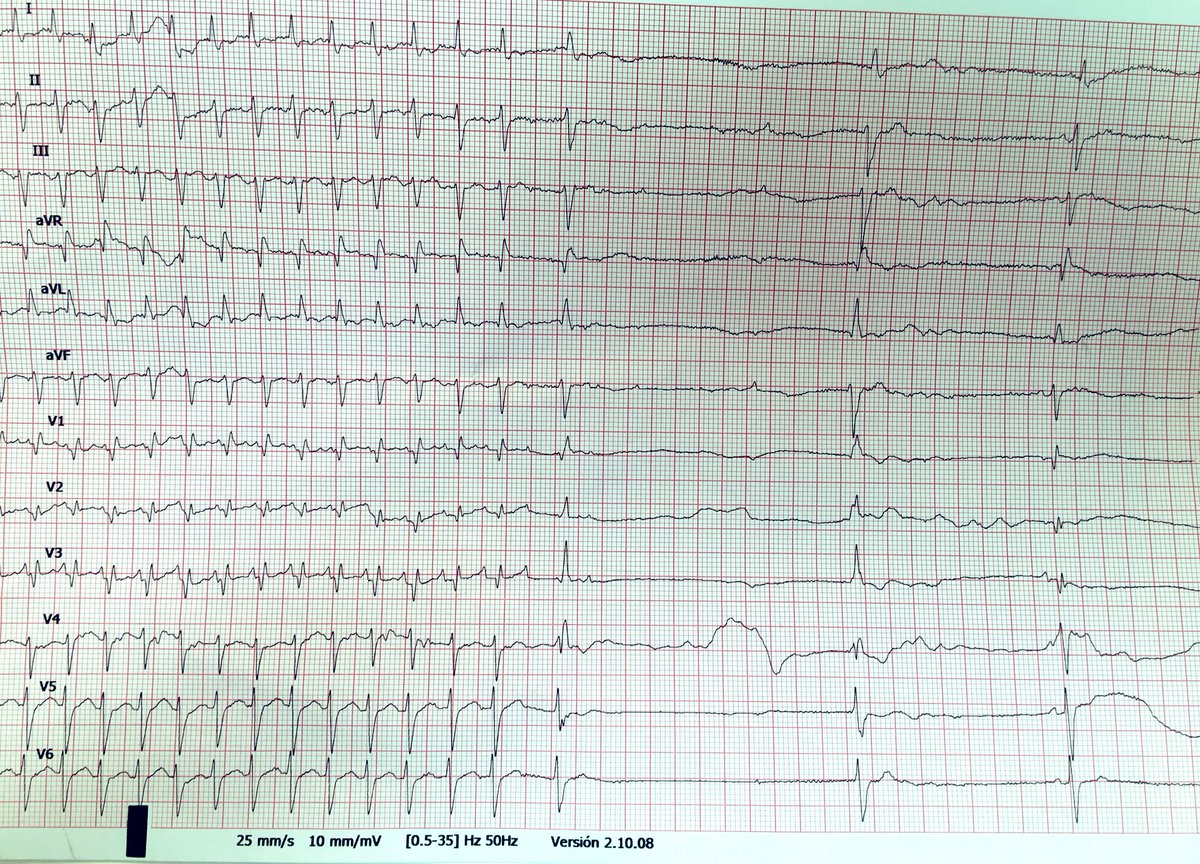

#SienteTuRitmo | En el marco del #PulseDay, muy pronto compartiremos una nueva historia de #ParteDeMí centrada en la concienciación sobre las arritmias cardiacas y la fibrilación auricular.

🫀Cada latido cuenta.